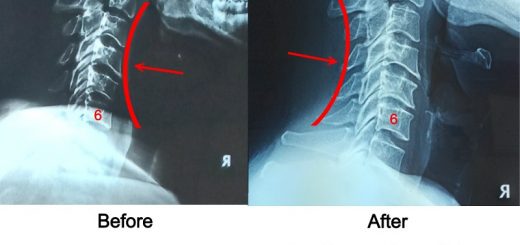

10 year old hunching back

C6 and C7 Cervical Nerve Compression